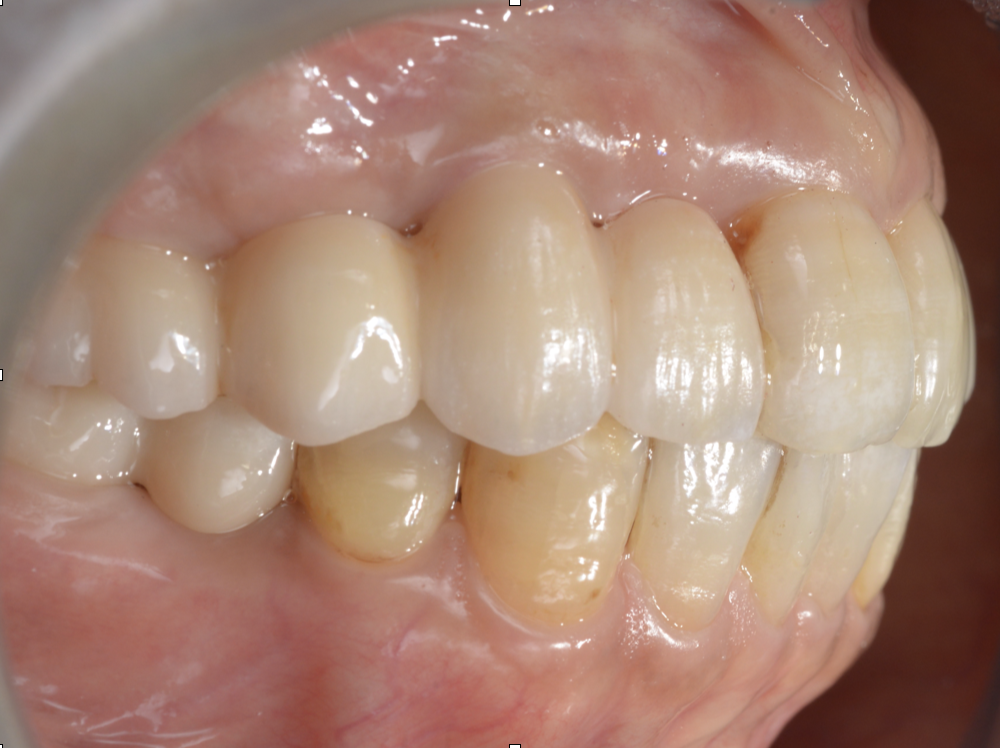

- ブリッジは高強度ジルコニアを選択し、審美性よりも厚みと強度を確保

治療の工夫②:上下ともにインプラントブリッジで機能を回復

上下ともにブリッジ設計とすることで、噛む機能を回復しながら

設計の自由度と安定性を確保しました。

ただし、ブリッジは材料選択と厚みの設計が重要です。

治療の工夫③:高強度ジルコニアを選び、審美より“強度と厚み”を優先

今回は、患者様が「噛めるようになりたい」という機能回復を最重視していたこと、

またブリッジ設計であることから、強度の高いジルコニアを選択しました。

高強度ジルコニアは、立体感や審美性(透明感)の表現がやや制限される一方で、

- 強度を確保しやすい

- ブリッジでの破折リスクを下げやすい

- 厚みを取って設計できるというメリットがあります。

今回は、理想的な審美表現よりも、厚みを確保して長期安定に寄せる設計にしています。